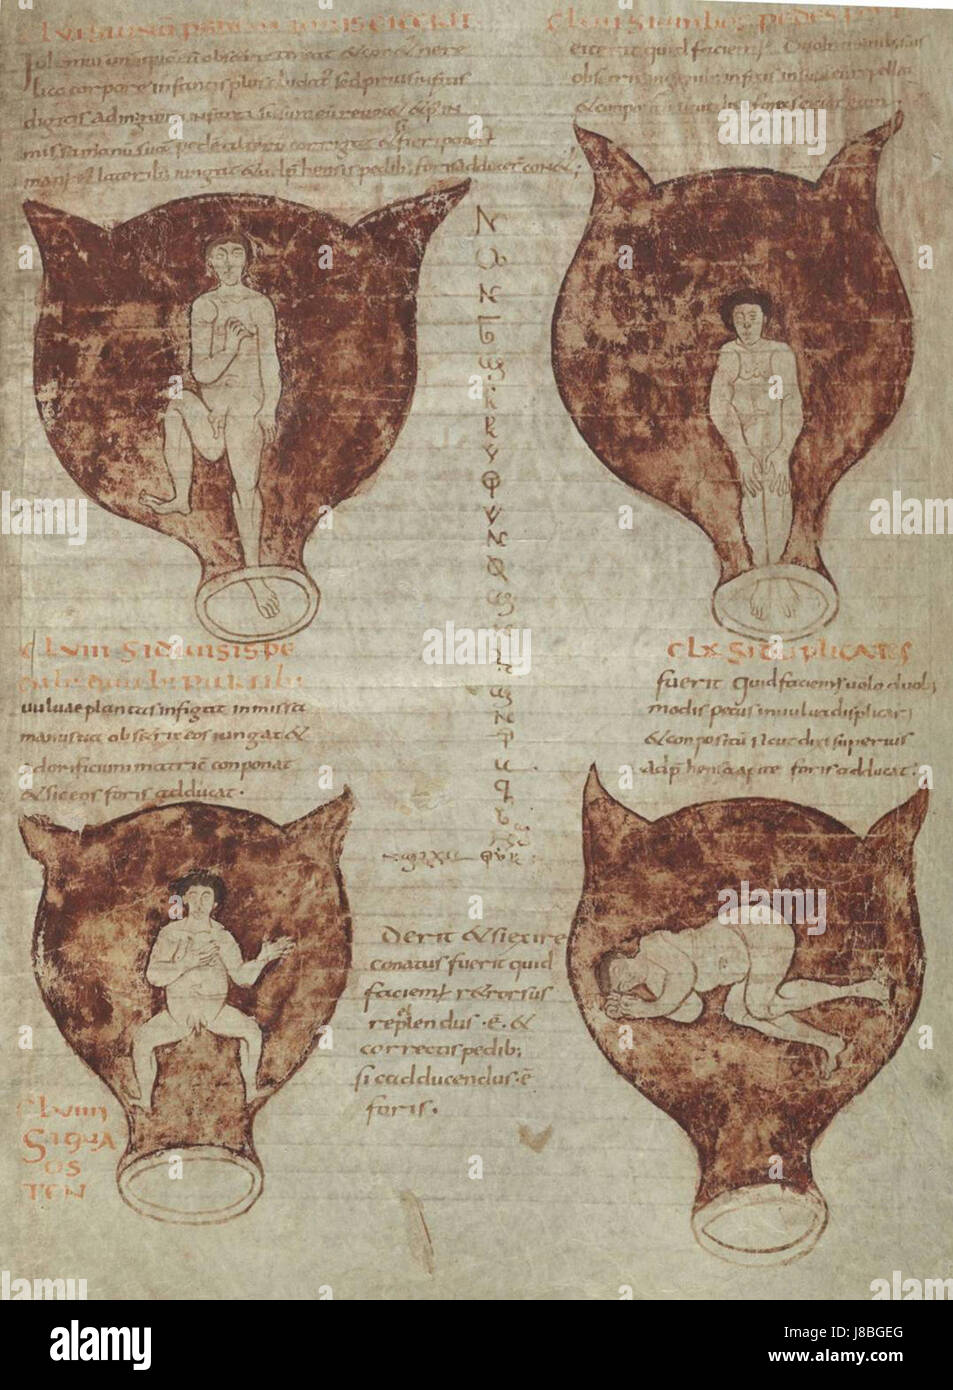

Foetal positions BR 3701 15 28r Stock Photohttps://www.alamy.com/image-license-details/?v=1https://www.alamy.com/stock-photo-foetal-positions-br-3701-15-28r-142854616.html

Foetal positions BR 3701 15 28r Stock Photohttps://www.alamy.com/image-license-details/?v=1https://www.alamy.com/stock-photo-foetal-positions-br-3701-15-28r-142854616.htmlRMJ8BGEG–Foetal positions BR 3701 15 28r

. English: Soranus of Ephesus, Gynaecology, in a Latin version of Late Antiquity: positions of the embryo in the uterus. The illustrations in this medieval manuscript are probably based on drawings by Soranus. Brussels, Bibliothèque Royale, Codex 3714, fol. 28r. Deutsch: Soranos von Ephesos, Gynäkologie, in einer spätantiken lateinischen Bearbeitung: Darstellungen von Kindslagen (Embryonen im Uterus). Die Abbildungen in dieser mittelalterlichen Handschrift gehen wohl ursprünglich auf Zeichnungen des Soranos zurück. Bruxelles, Bibliothèque Royale, Codex 3714, fol. 28r. circa 900. Soranus of Eph Stock Photohttps://www.alamy.com/image-license-details/?v=1https://www.alamy.com/english-soranus-of-ephesus-gynaecology-in-a-latin-version-of-late-antiquity-positions-of-the-embryo-in-the-uterus-the-illustrations-in-this-medieval-manuscript-are-probably-based-on-drawings-by-soranus-brussels-bibliothque-royale-codex-3714-fol-28r-deutsch-soranos-von-ephesos-gynkologie-in-einer-sptantiken-lateinischen-bearbeitung-darstellungen-von-kindslagen-embryonen-im-uterus-die-abbildungen-in-dieser-mittelalterlichen-handschrift-gehen-wohl-ursprnglich-auf-zeichnungen-des-soranos-zurck-bruxelles-bibliothque-royale-codex-3714-fol-28r-circa-900-soranus-of-eph-image188858543.html

. English: Soranus of Ephesus, Gynaecology, in a Latin version of Late Antiquity: positions of the embryo in the uterus. The illustrations in this medieval manuscript are probably based on drawings by Soranus. Brussels, Bibliothèque Royale, Codex 3714, fol. 28r. Deutsch: Soranos von Ephesos, Gynäkologie, in einer spätantiken lateinischen Bearbeitung: Darstellungen von Kindslagen (Embryonen im Uterus). Die Abbildungen in dieser mittelalterlichen Handschrift gehen wohl ursprünglich auf Zeichnungen des Soranos zurück. Bruxelles, Bibliothèque Royale, Codex 3714, fol. 28r. circa 900. Soranus of Eph Stock Photohttps://www.alamy.com/image-license-details/?v=1https://www.alamy.com/english-soranus-of-ephesus-gynaecology-in-a-latin-version-of-late-antiquity-positions-of-the-embryo-in-the-uterus-the-illustrations-in-this-medieval-manuscript-are-probably-based-on-drawings-by-soranus-brussels-bibliothque-royale-codex-3714-fol-28r-deutsch-soranos-von-ephesos-gynkologie-in-einer-sptantiken-lateinischen-bearbeitung-darstellungen-von-kindslagen-embryonen-im-uterus-die-abbildungen-in-dieser-mittelalterlichen-handschrift-gehen-wohl-ursprnglich-auf-zeichnungen-des-soranos-zurck-bruxelles-bibliothque-royale-codex-3714-fol-28r-circa-900-soranus-of-eph-image188858543.htmlRMMY76YY–. English: Soranus of Ephesus, Gynaecology, in a Latin version of Late Antiquity: positions of the embryo in the uterus. The illustrations in this medieval manuscript are probably based on drawings by Soranus. Brussels, Bibliothèque Royale, Codex 3714, fol. 28r. Deutsch: Soranos von Ephesos, Gynäkologie, in einer spätantiken lateinischen Bearbeitung: Darstellungen von Kindslagen (Embryonen im Uterus). Die Abbildungen in dieser mittelalterlichen Handschrift gehen wohl ursprünglich auf Zeichnungen des Soranos zurück. Bruxelles, Bibliothèque Royale, Codex 3714, fol. 28r. circa 900. Soranus of Eph